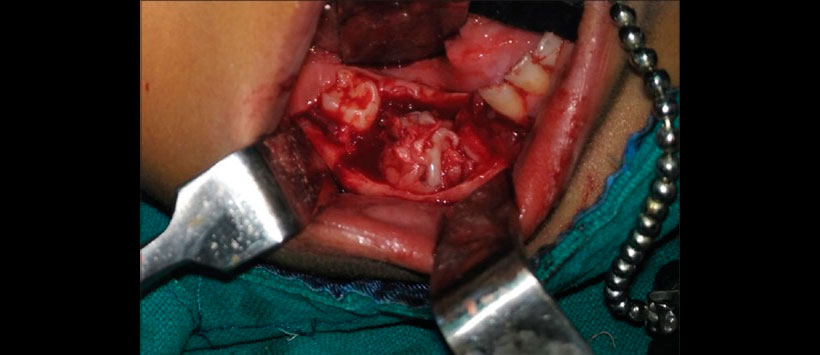

Figura 3: Fotografía intraoperatoria que muestra la masa tumoral